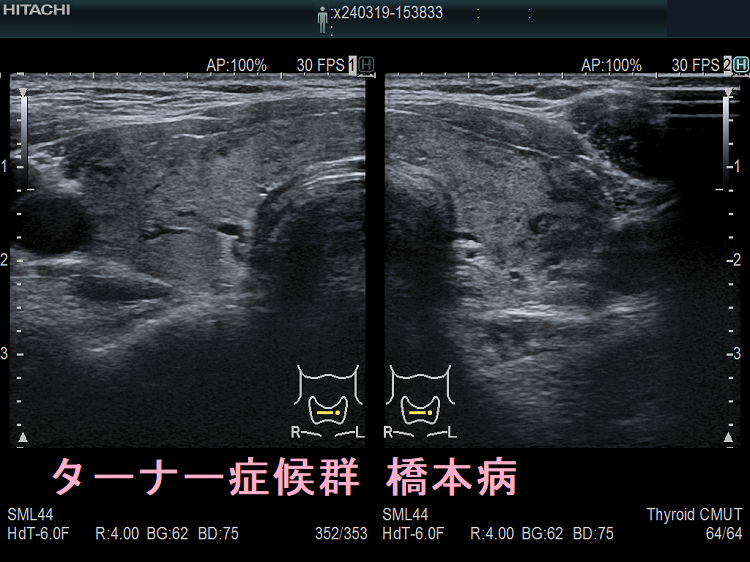

ターナー症候群と橋本病(TURNER SYNDROME FOUNDATION HPより改変)

ターナー症候群では甲状腺の病気(甲状腺機能亢進症、甲状腺機能低下症/橋本病)の合併率が高い(43.8%)とされます。(J Pediatr Endocrinol Metab. 2015 Jan;28(1-2):201-5.)(J Endocrinol Invest. 2011 Apr;34(4):260-4.)

6~18歳のターナー症候群女子において、26.8%で抗甲状腺ペルオキシダーゼ抗体(TPO抗体)、抗サイログロブリン抗体(Tg抗体)のいずれか、あるいは両方が陽性。(Adv Exp Med Biol. 2017;1022:71-76.)